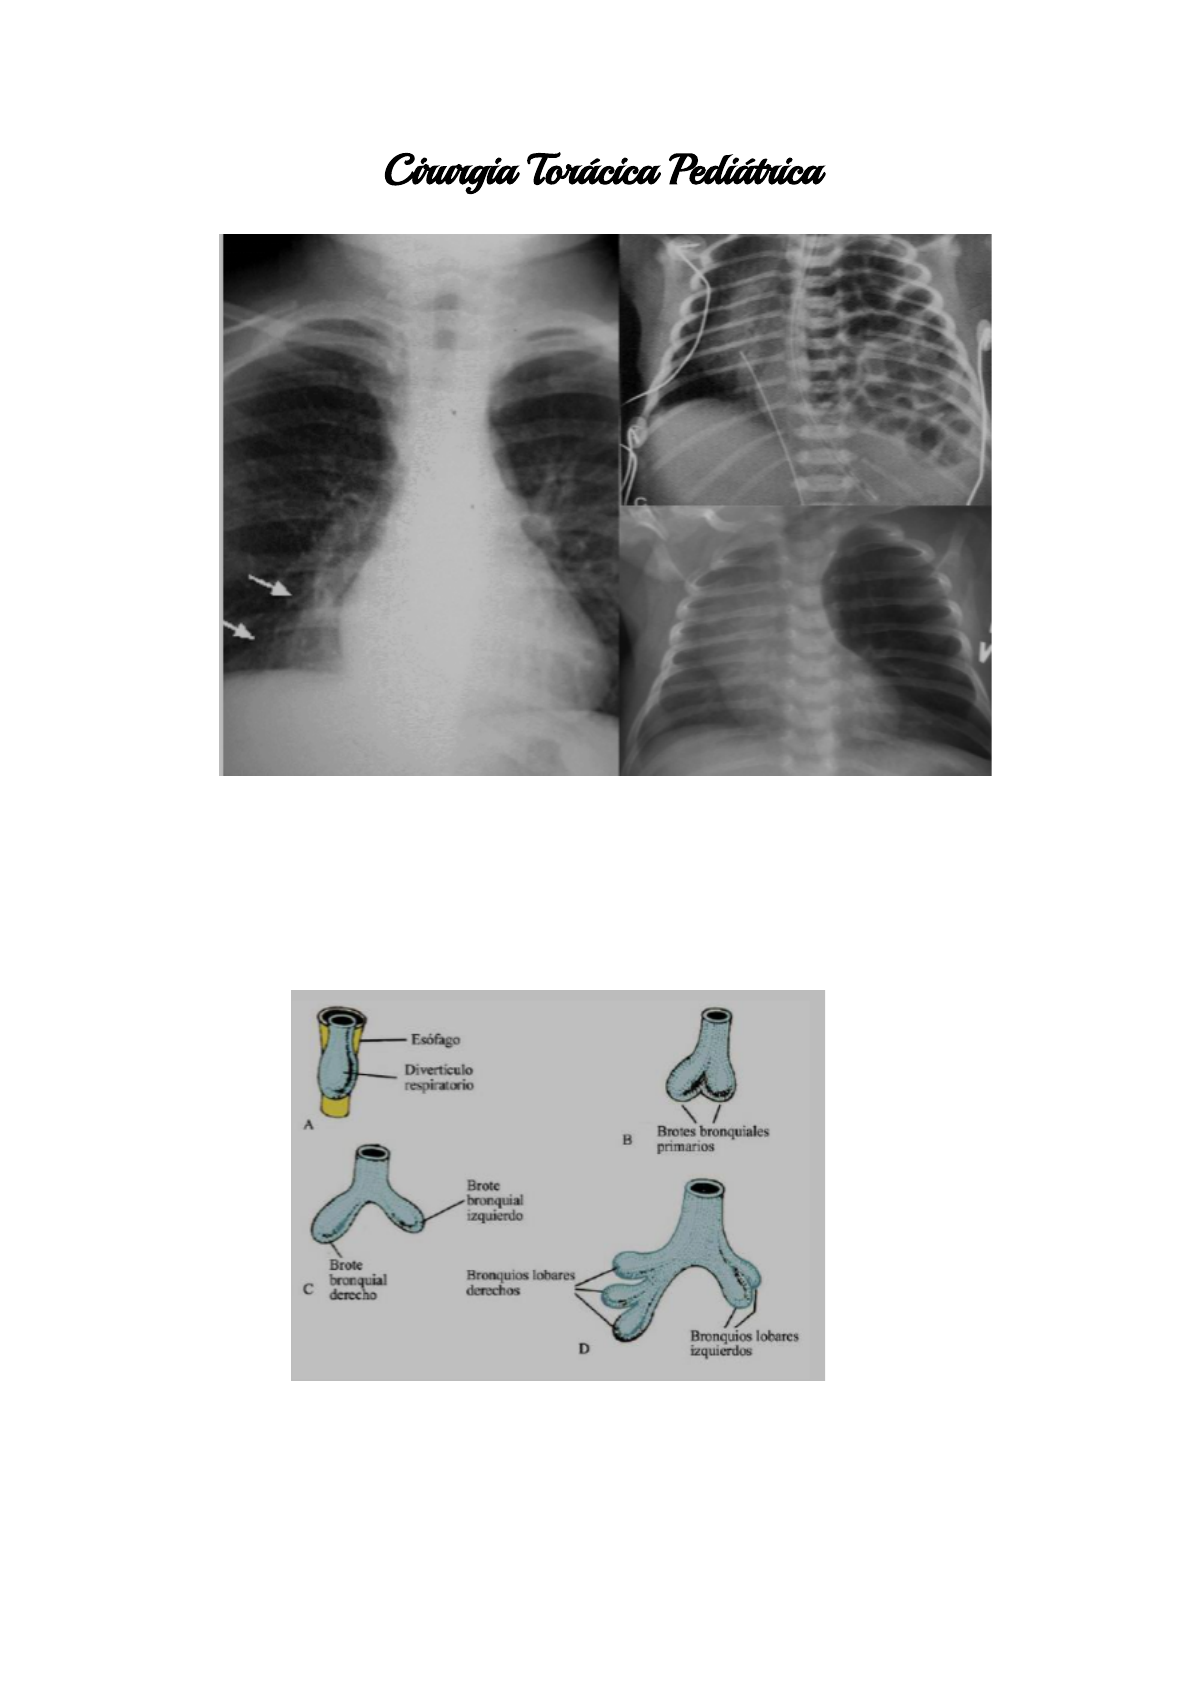

● Embriologia:

○ 3ª semana: intestino anterior-tubo, broto traqueal

○ 4 - 5ª semanas: septação esôfago e traqueia.

○ 4ª semana: diferenciação do epitélio traqueal e esofágico.

○ tubularização incompleta do epitélio intestinal: duplicação cística.

○ pulmão: 5 estágios - embriônico, pseudoglandular (7 - 16ª semana),

canalicular (16 - 24ª semana), sacular e alveolar.

A: lesão em ápice direito

RX: lesão central e cística

B: hiperaeração